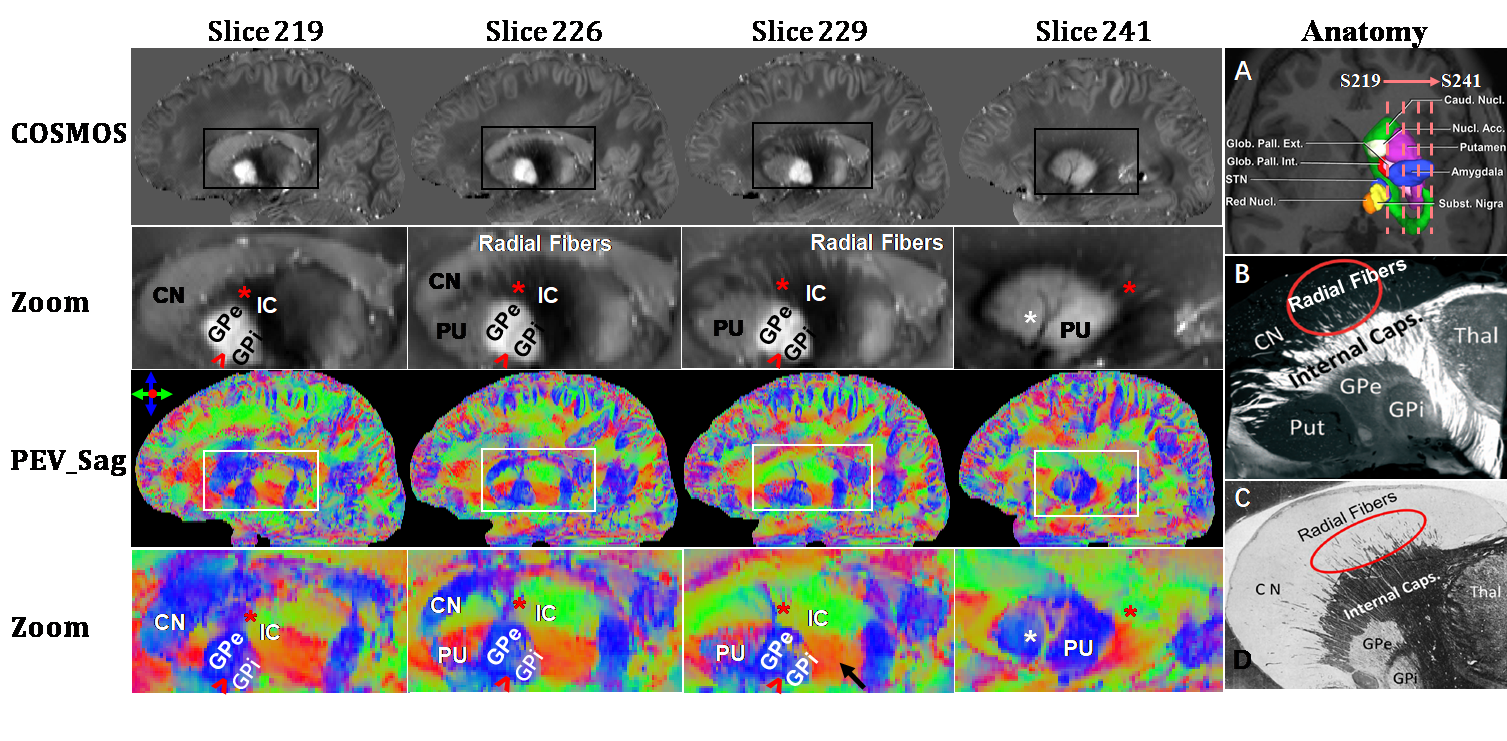

图1.活体人脑磁化率成像及脑组织结构的矢状面视图

图1第一、二行是一组磁化率的标量图及方框区域的局部放大。第三、四行是由磁化率张量导出的纤维方向彩色编码图及局部放大。最后一列为参照信息,是神经解剖学中基底节结构的体视图和层切片光学显微图。*指示投射纤维Radial fibers,^指示将苍白球分为内侧苍白球GPi和外侧苍白球GPe的内侧髓板。PU:壳核,CN:尾状核,IC:内囊。图中可见基底节的内部投射纤维束和内侧髓板,这些是其它活体磁共振成像方法难以检测到的微结构。